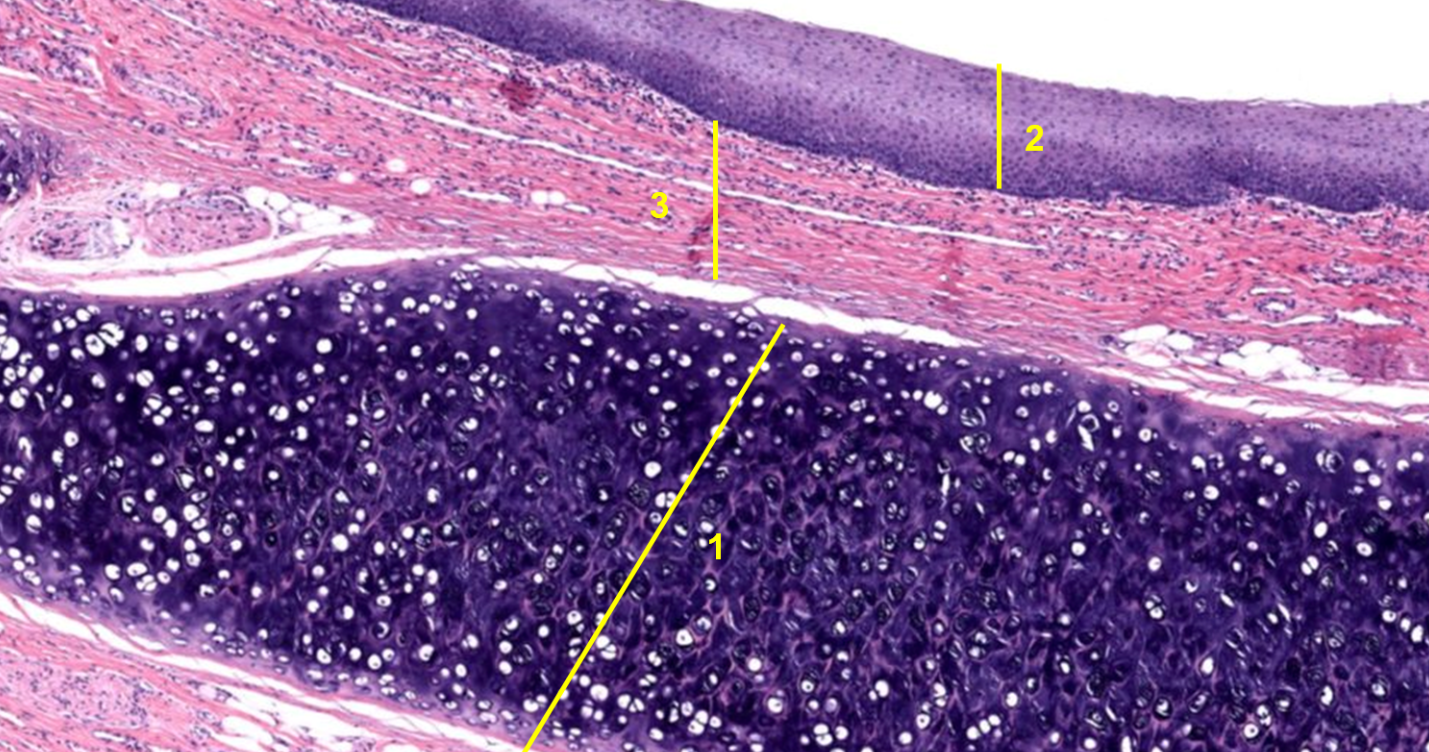

1: Córnea

2: Íris

3: Lente / Cristalino

Córnea